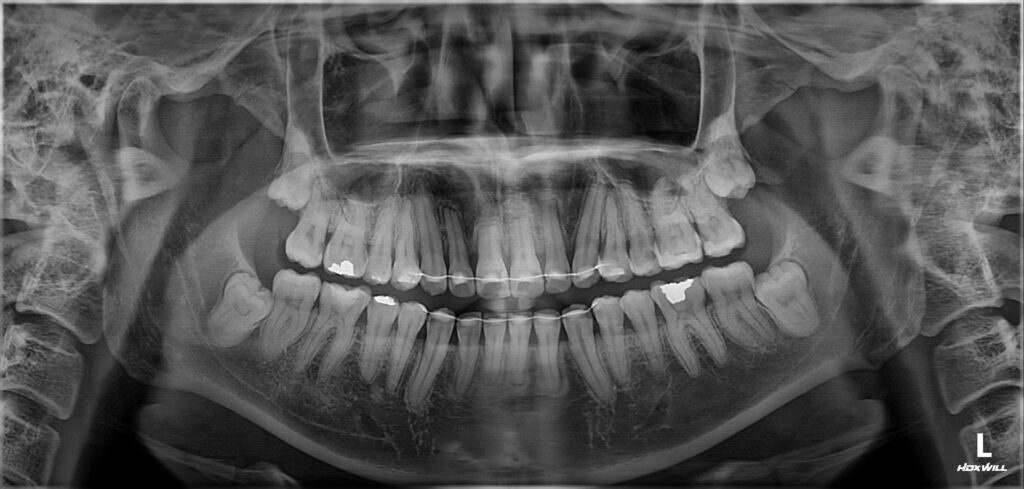

먼저 심미적인 개선이 가장 중요한

위쪽 송곳니부터 송곳니까지

총 6개의 전치부에 대해 e.max empress

라미네이트 베니어를 적용하였습니다.

이어서 나머지 치아에서는 치경부 우식 부위를

중심으로 복합레진 수복을 시행하여

손상된 부위를 보존하고 추가적인 진행을 방지하였습니다.

또한 우식 범위가 넓거나 교합 부담이

큰 부위에는 인레이 치료를 적용하여

내구성을 확보하였고,

치수까지 영향을 받은 치아에 대해서는

근관치료를 선행한 후 크라운으로

최종 수복을 진행하였습니다.

전체적으로 인레이 6개, 근관치료 1개,

크라운 2개, 레진 6개 등 총 20개 치아에 대한

치료가 이루어졌으며,